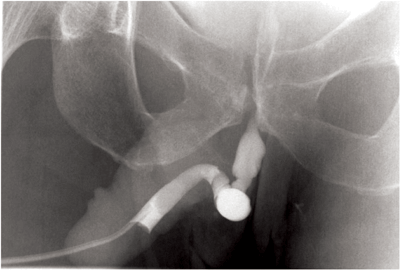

If the catheter isn’t flushed prior to inserting it into the urethra then air bubbles can be present and can be difficult to distinguish from true pathology (Figure 2).

Figure 2: Beware of air bubbles (arrows) being confused as pathology.

Always flush the catheter before placing it in the urethra.